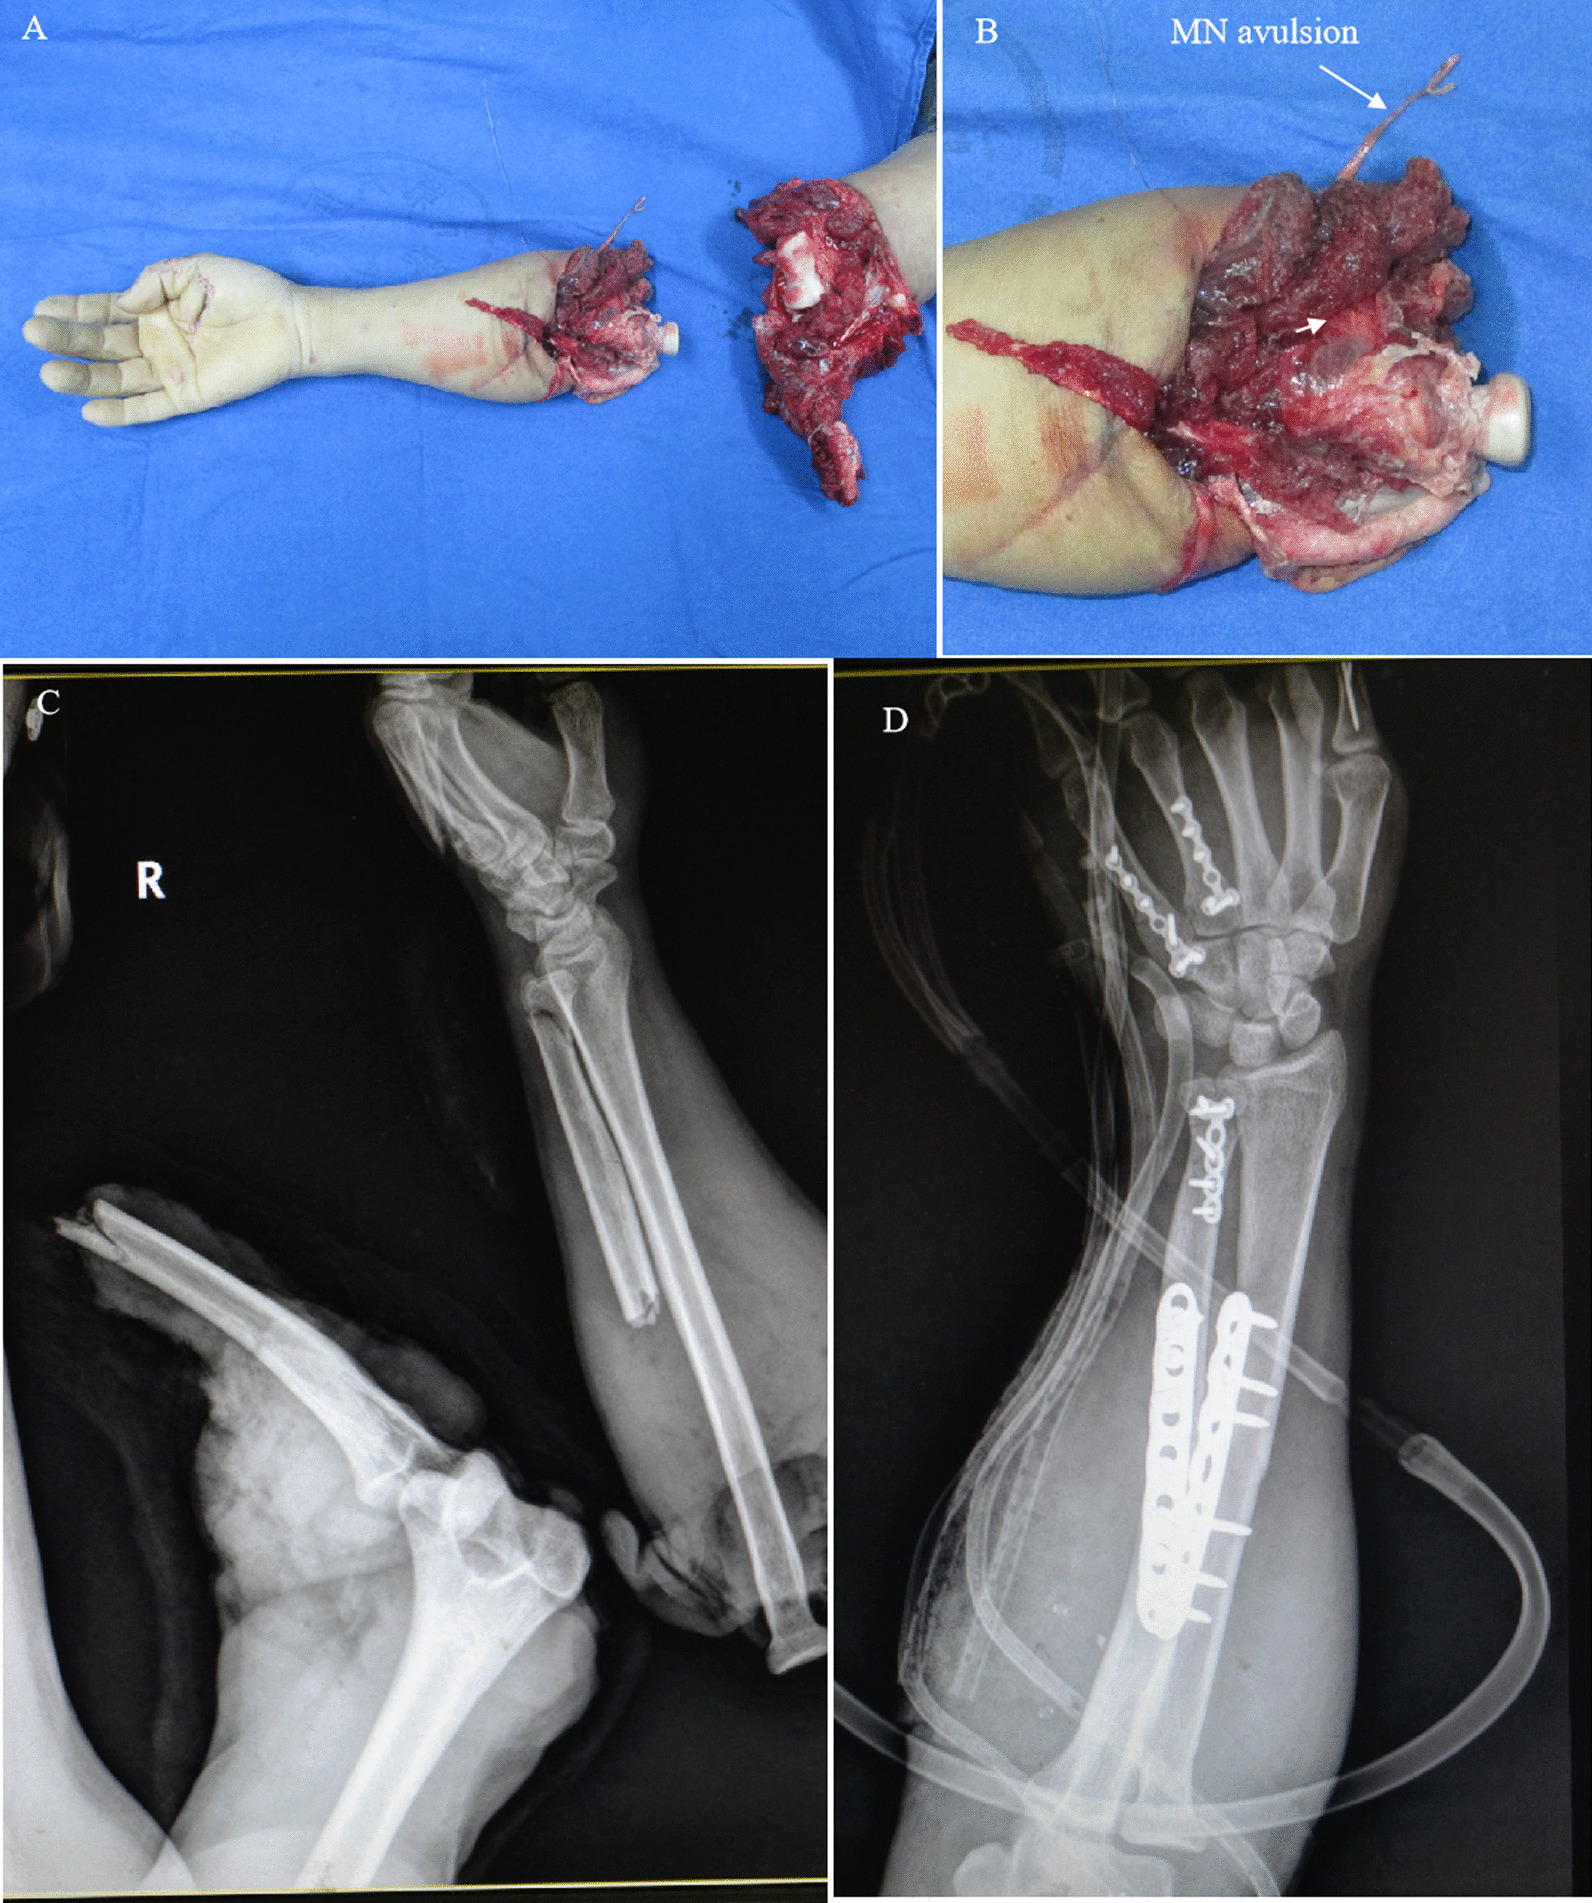

Figures 7, 8 and 9 show the treatment process of a patient (case 2) undergoing M-(M + U) repair. The patient showed the following signs: deep RN branch defects, superficial RN branch ruptures, avulsion and long-segment MN and UN loss, and a relatively intact proximal MN end. Based on these findings, M-(M + U) repair was proposed. Autogenous nerve transplantation was first performed for the RN before coaptation was conducted to facilitate innervation of the distal ends of the MN and UN by the MN.

Fig. 7.

A patient (case 2) undergoing M-(M + U) repair (part 1). A, B The subject suffered avulsion amputation of the elbow joint and MN and UN in the right upper limb. C Preoperative X-ray showed that the subject had elbow joint dislocation and multiple fractures of the ulna and metacarpal bones. D Postoperative X-ray showed internal fixation of the ulna and metacarpal fractures, shortening and internal fixation of the radius, and reduction of the elbow joint